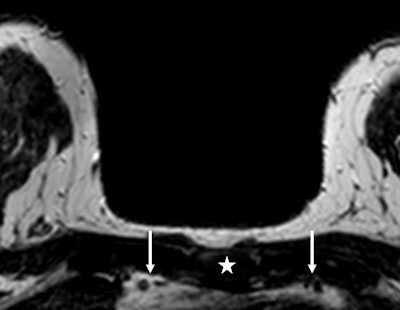

In healthy women, the breast is mainly perfused by the internal mammary artery (IMA), according to Dr. Robert-Jan Schipper from the department of surgery at Maastricht University Medical Center, the Netherlands, and colleagues. It's a paired artery, one running on the left side of the sternum and one on the right side.

"We hypothesized that if a malignant lesion is present the cross-sectional area of the IMA and/or internal mammary veins (IMV) on the side of the lesion is increased compared to the healthy side," they wrote. "Measuring and comparing the left and right IMA and IMV could only be useful if the cross-sectional areas of these vessels in a healthy person without breast malignancy are similar."

The cross-sectional areas of the IMA and IMV were measured on the left and right side in the second and third intercostal space (ICS) of 135 breast MRIs by two independent readers.

In the healthy control group (n = 91) no significant differences were observed between the cross-sectional areas of the IMA and IMV. Both readers reported a mean adjusted difference of 0.12 mm2 and 0.21 mm2 for the IMA in the second intercostal space.

In the malignancy group (n = 44), the cross-sectional area was significantly larger on the malignancy side compared with the contralateral side. The largest difference in the IMA was measured in the second intercostal space with a mean adjusted difference for reader one of 1.37 mm2 and 0.81 mm2 for reader two.